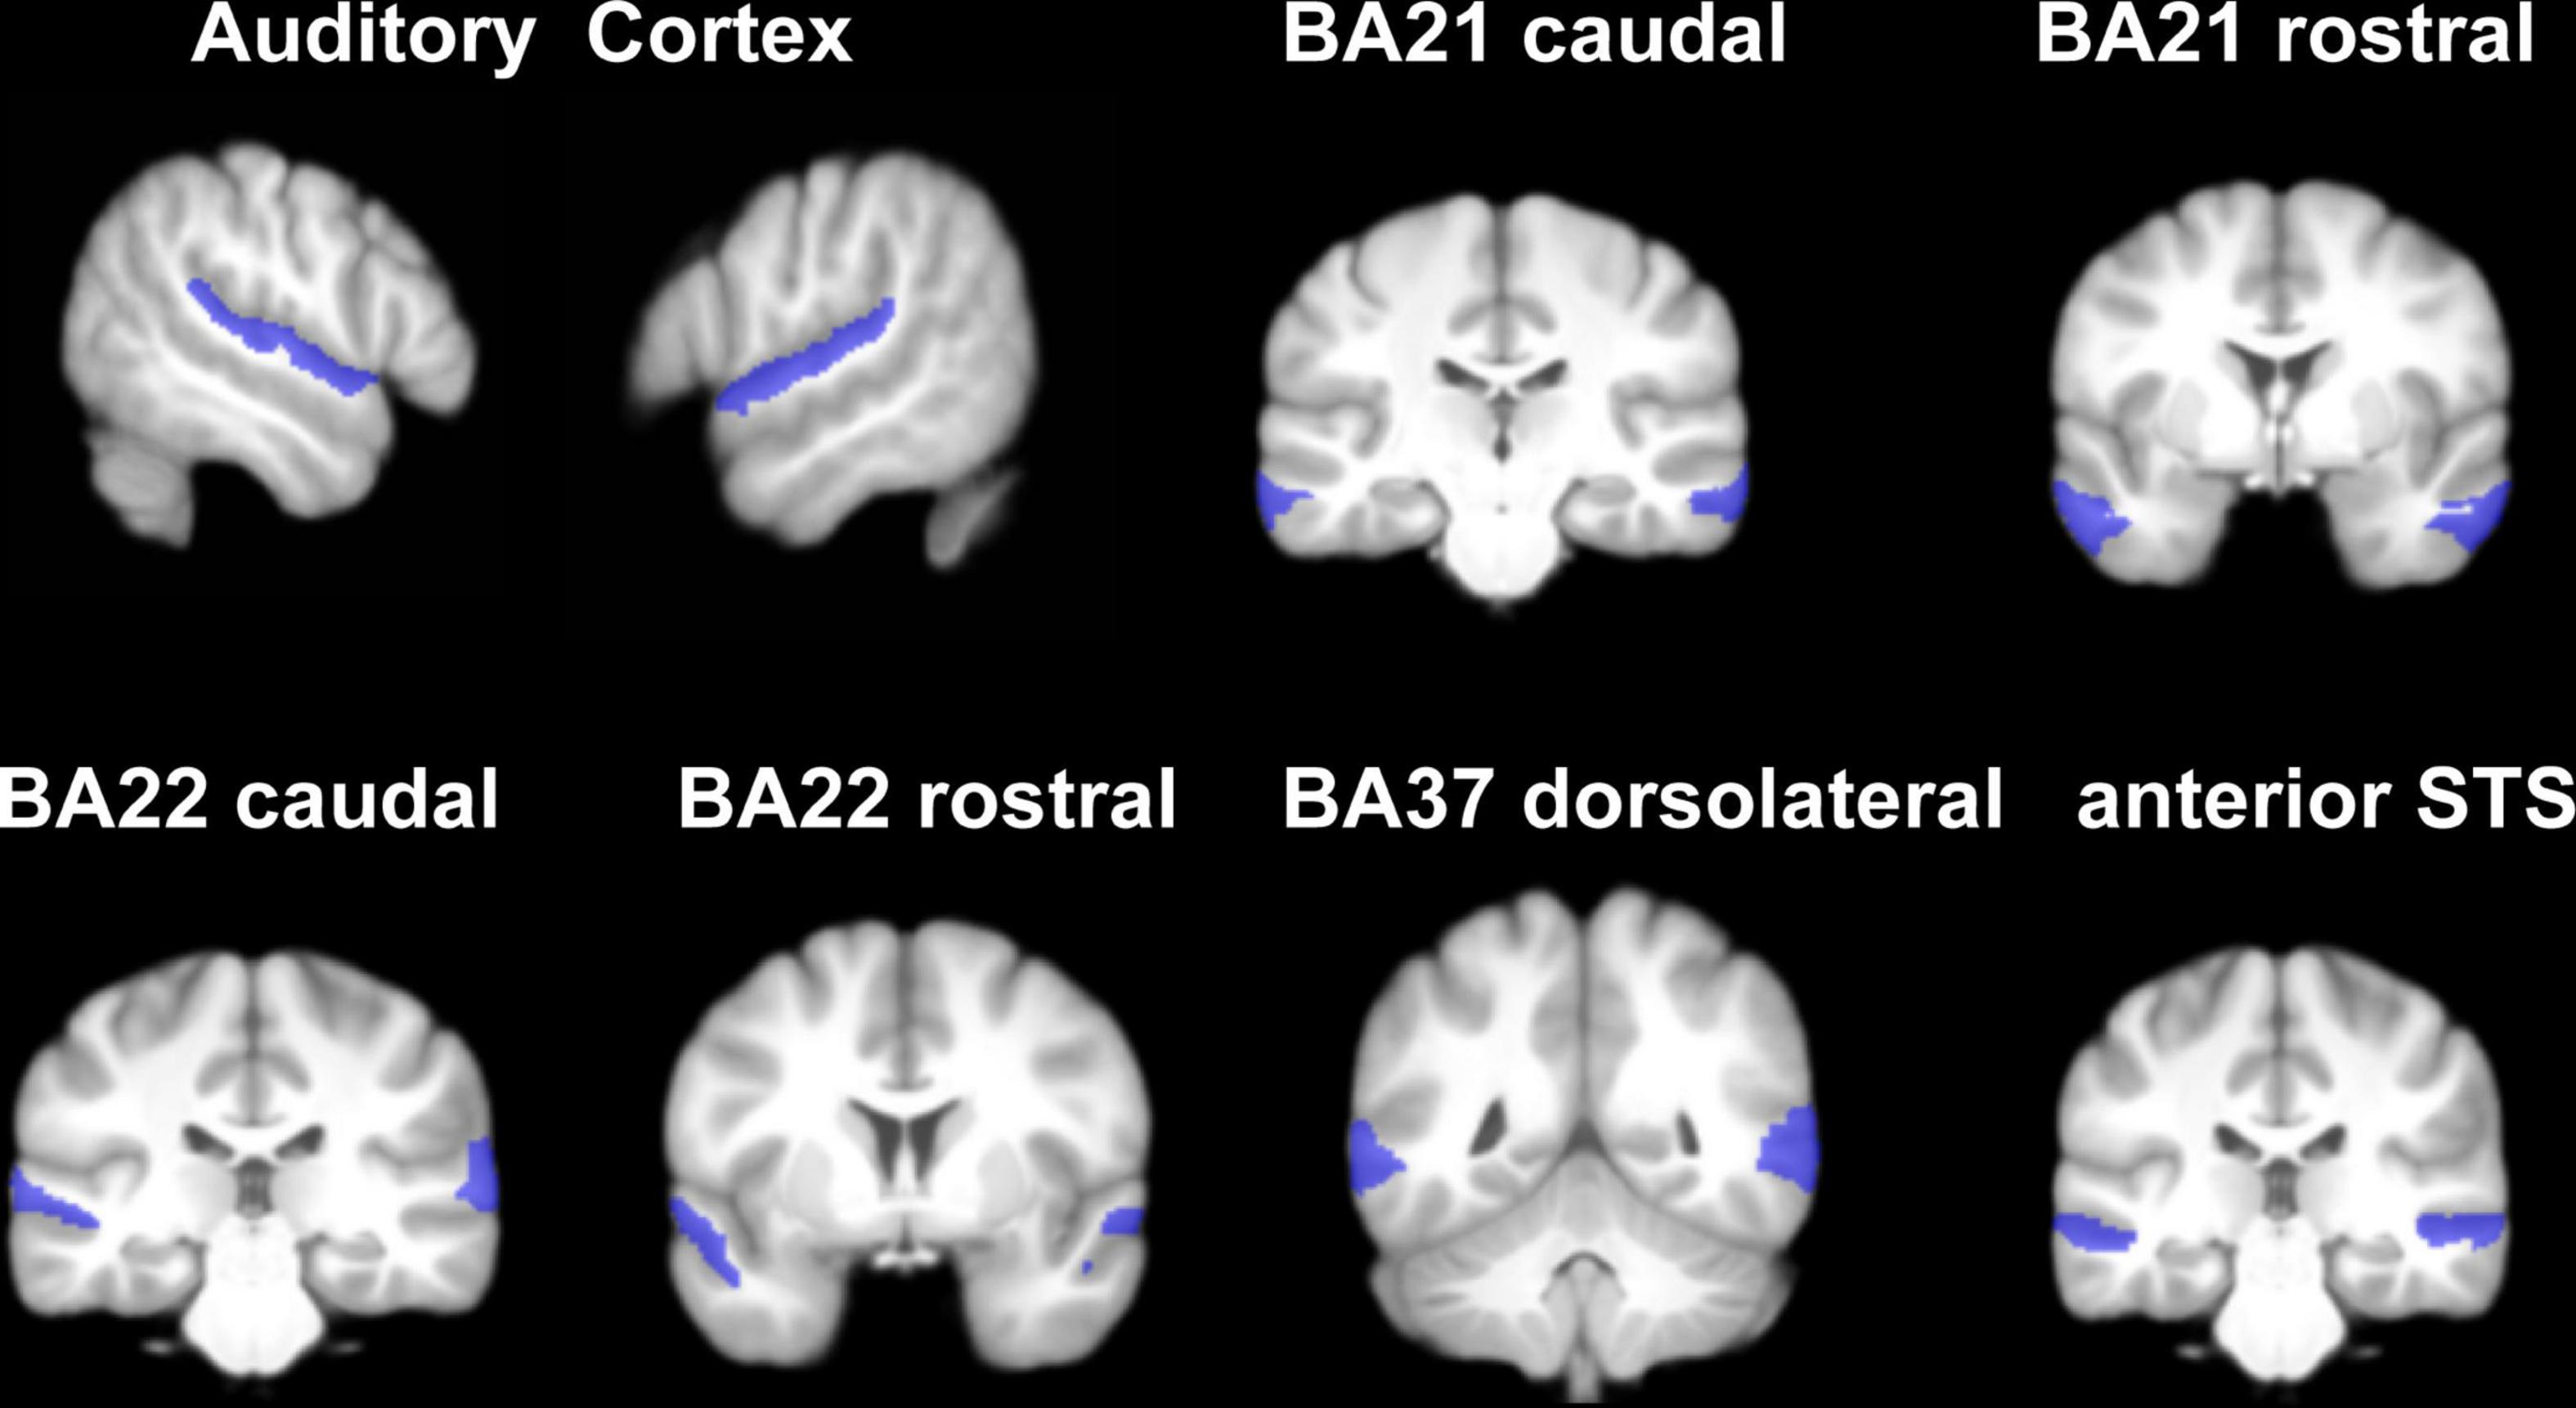

Several studies have confirmed changed neuronal activity of the auditory cortex in SSNHL patients (Minosse et al., 2020; Zou et al., 2021). Considering the lateralization effects of auditory cortex (Tervaniemi and Hugdahl, 2003), we investigated the CBF differences of auditory-related areas among lSSNHL, rSSNHL, and HCs. We conducted an ROI analysis of auditory-related areas for further analysis. Auditory related areas of both hemispheres with in BNA were divided into the following ROIs: auditory cortex (BA41/42; TE1.0 and TE1.2), Wernicke’s area (BA22 caudal and rostral) and associative auditory areas (BA21 caudal and rostral; BA37 dorsalateral; and the anterior part of the Superior Temporal Sulcus) (Martín-Fernández et al., 2021; Figure 2).